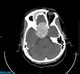

Paranasal sinusitis

Sinusitis, also known as rhinosinusitis, is inflammation of the mucous membranes that line the sinuses resulting in symptoms that may include thick nasal mucus, a plugged nose, and facial pain. Other signs and symptoms may include fever, headaches, a poor sense of smell, sore throat, and a cough. [Source: Wikipedia ]